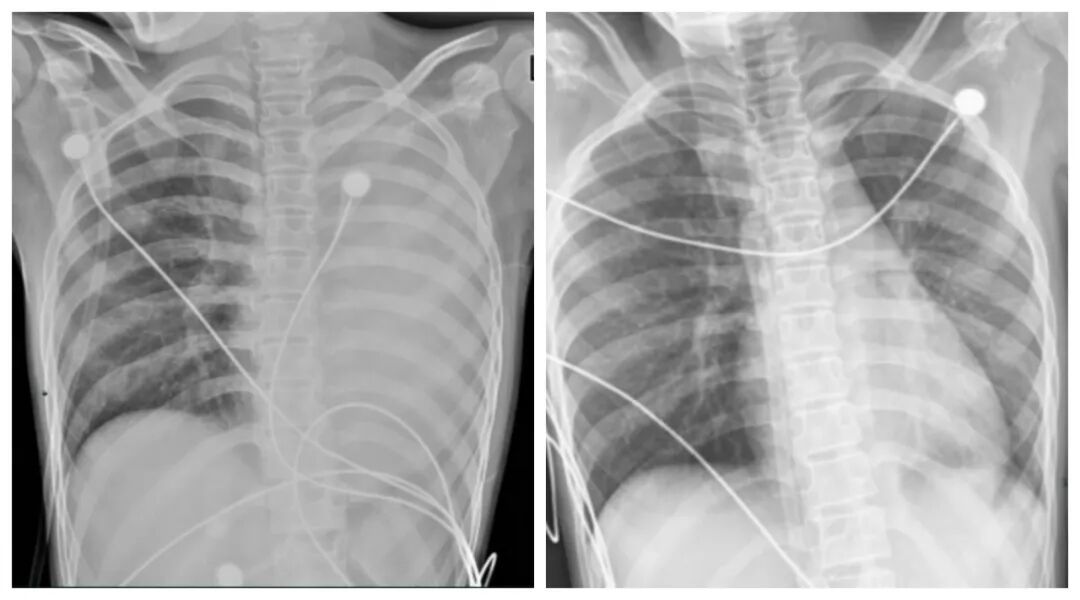

一开始,她只是轻微咳嗽,发热后在外院检查提示肺炎、肺不张,转诊到浙大四院儿科时,笑笑出现呼吸急促、胸闷胸痛,血氧饱和度勉强维持在 90% 左右,胸片显示左肺已完全呈 “白肺” 改变,病情急剧恶化。

笑笑治疗前,左肺呈“白肺”状态,治疗后“白肺”被吸收,心脏边缘清晰可见。图源:浙大四院

术后第二天,笑笑呼吸困难、胸痛的症状明显好转,病情得到了初步控制。经过精准抗感染、祛痰、抗炎等系列治疗,笑笑逐渐康复,顺利出院。